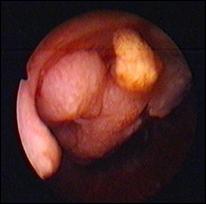

6. Diagnosticul diferential cu leziuni vezicale benigne

Aspecte cistoscopice de cistita chistica